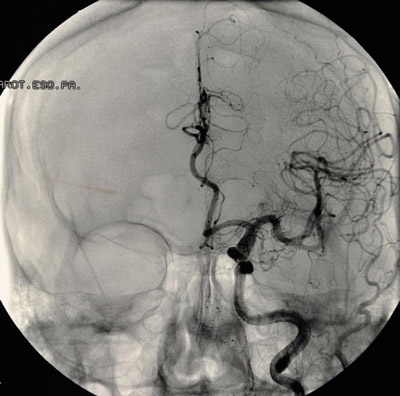

Доступ к аневризме при эндоваскулярной операции осуществляется через бедренную артерию, в которую вводится катетер. Он доставляет к аномальным сосудам баллон или специальные спирали, которые останавливают кровоток в образовании. Также могут применяться стенты, блокирующие аневризму, но позволяющие крови свободно циркулировать по основным сосудам мозга.

Сначала в полость аневризмы вводится самая крупная спираль, затем пространство заполняется более мелкими, способствующими образованию тромба и исключающими аневризму из кровотока. Если шейка питающего сосуда широкая, установка спиралей дополняется стентированием.

Одним из вариантов эндоваскулярного лечения является эмболизация сосудов аневризмы, при которой стенки склеиваются с помощью спирта, хирургического геля или специальных составов. Для полного устранения аневризмы может потребоваться несколько таких процедур.

В процессе операций на сосудах мозга применяются операционный микроскоп, специальный стол с фиксирующей скобой, а также эндоскопическая и микрохирургическая техника. Состояние кровотока контролируется с помощью микродатчиков ультразвукового исследования.